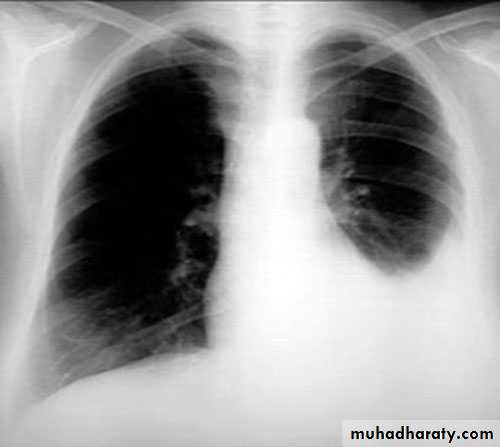

X-ray of pleural effusion

Massive right effusion